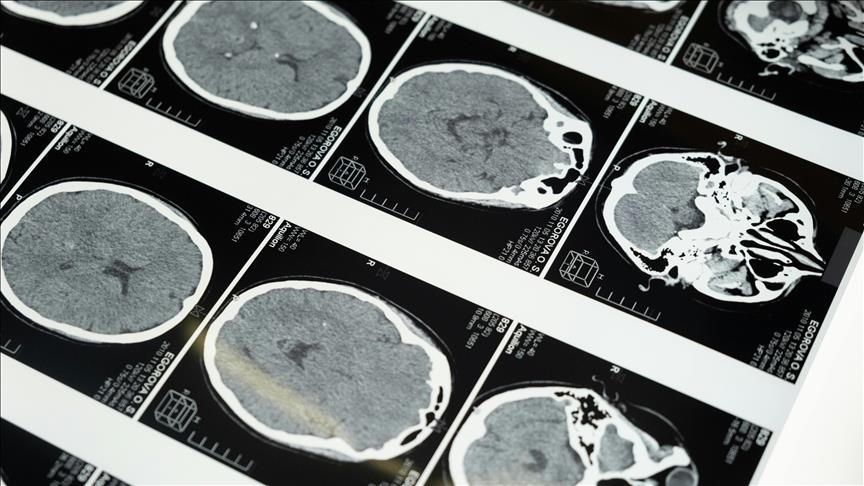

Bilim insanları, geliştirdikleri yeni yapay zeka yazılımı aracılığıyla inme geçiren hastaların beyin taramalarında inmenin ne zaman geçirildiği ve tedavi edilip edilemeyeceğinin normalden 2 kat daha doğru tespit edilebildiğini açıkladı.

Araştırmacılar yazılımın, beyin taramasında ilgili alanı otomatik olarak çıkarmanın yanı sıra, tanımlanan lezyonları analiz ederek inme geçirilen zamanı tahmin edebildiğini tespit etti.

Araştırmacılar, yeni yapay zeka yazılımı kullanılarak yapılan taramaların doku gibi ek özellikler içermesi ve lezyonlardaki varyasyonları hesaba katmasının daha önce kullanılan tarama yöntemlerine kıyasla daha iyi sonuç alınmasında etkili olduğunu belirtti.